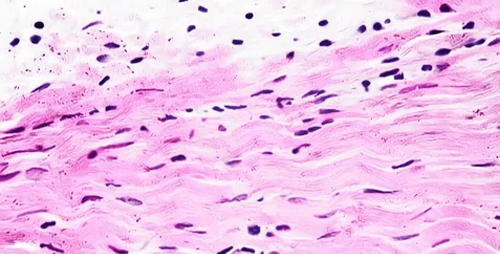

Para realizar este estudio se necesita una muestra de piel.

La muestra de piel se obtiene por biopsia del brazo, se cultivan los fibroblastos que son células que al entrar en división proporcionan los cromosomas para estudiarlos.